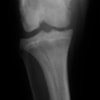

術前正面像

術後左後肢正面像